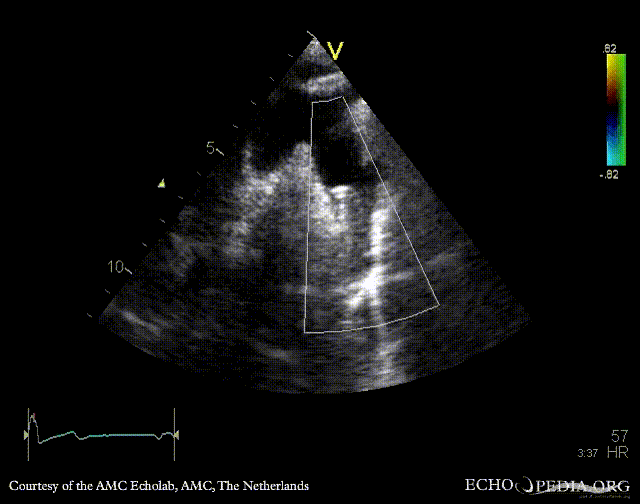

Suprasternal view: stent in aorta descendends, status after correction of coarctatio aortae Suprasternal view with color doppler